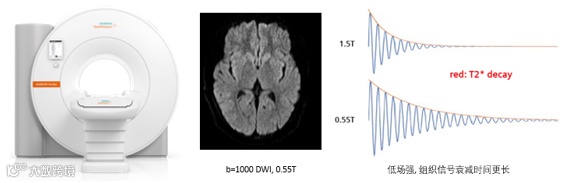

全球首台水平磁场0.55T超导磁共振MAGNETOM Free.Ma,兼顾中等场强组织信号衰减时间更长和水平磁场高信噪比、高加速因子等优势,获得超出预期想象的临床图像质量和科研表现。